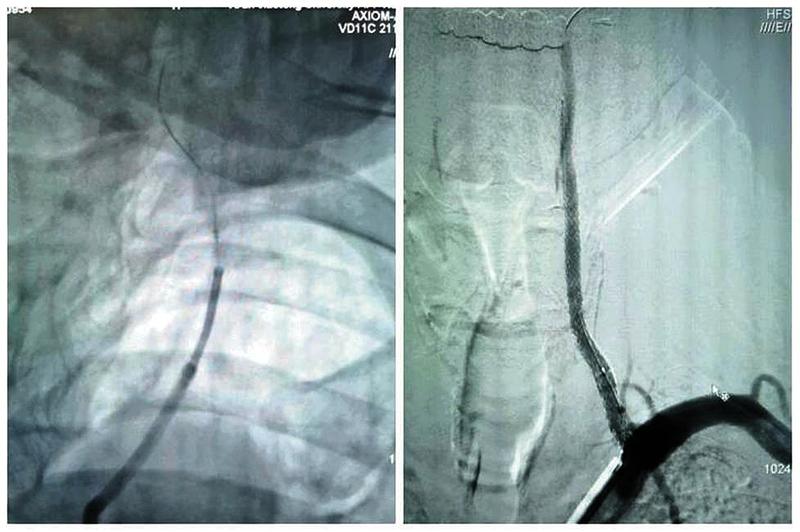

最终,在患者入院第4天,张桂莲教授带领的介入团队选择局麻条件下为患者成功实施了神经介入领域的高难度手术—左侧无残端椎动脉长节段慢性闭塞再通术。因术前清晰的影像显影及准确的体外定位标记,左侧优势椎动脉顺利开通,手术耗时仅仅约90分钟。术中及术后患者配合良好,无任何不适。出院前复查头颈一体化超声提示左侧椎动脉支架位置良好,血流通畅,颅内血流速度及频谱未见明显异常。充分向患者及家属告知出院注意事项及复查时间后,目前该患者已顺利出院。